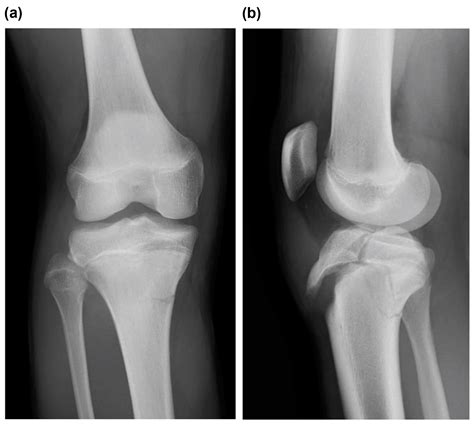

To confirm the diagnosis, medical professionals typically utilize imaging studies. X-rays are the gold standard for visualizing the displaced bone fragment and determining the severity of the fracture. In more complex or comminuted cases, an MRI may be ordered to assess the condition of the surrounding soft tissues, including the patellar tendon and menisci.

• Deformity: A visible or palpable gap or bump may be present at the site of the injury.

Orthopedic surgeons often categorize these injuries based on the Ogden classification system, which helps guide treatment decisions. This classification ranges from simple, non-displaced fractures to complex injuries that extend into the knee joint.